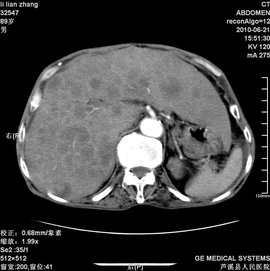

肝弥漫性病变

220x126 - 7KB - JPEG

肝弥漫性病变_360百科

270x271 - 15KB - JPEG